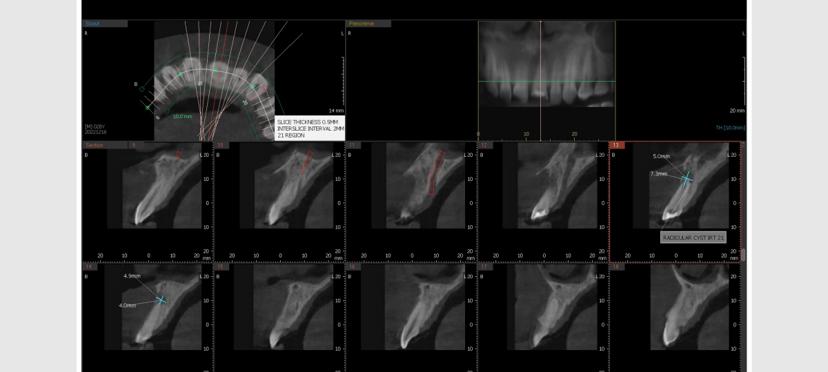

Cyst Diagnosis

Accurately identifies and locates cysts and other pathological lesions within the jaws and surrounding bone structures, aiding in proper treatment planning.

Cyst-Cross Sectional View

Cyst-Orthogonal Plane View